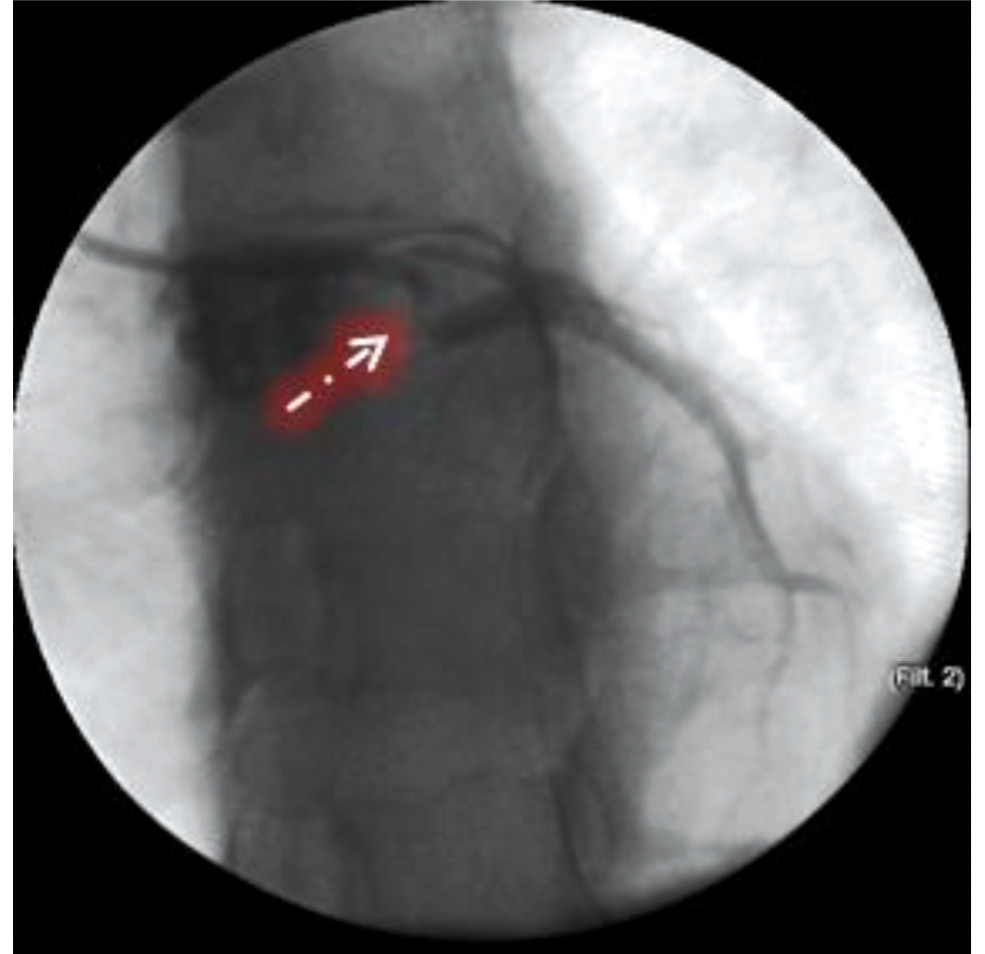

При установке проводникового катетера (ПК) EBU 3.5-6Fr отмечались технические сложности ввиду анатомических особенностей ЛКА (короткий ствол) и малого диаметра восходящего отдела аорты, что потребовало смены ПК на 3.5-6Fr. После этого в дистальные отделы ПМЖА был заведён коронарный проводник и произведена предилатация зоны субокклюзии баллонным катетером 2,0×20 мм при давлении 12 и 14 атм. На контрольной КАГ обнаружены повреждение интимы в приустьевом отделе ПМЖА с резким ограничением кровотока до TIMI I и диссекция в приустьевом отделе ОВ с формированием субинтимальной гематомы и ограничением кровотока до TIMI I, что клинически сопровождалось развитием ангинозного приступа (рис. 4).

Рис. 4. Контрольная коронарограмма пациентки К. Линейная диссекция в приустьевом отделе огибающей ветви левой коронарной артерии, возникшая при установке проводникового катетера.

Fig. 4. Control coronarogram. Linear dissection in the left circumflex coronary artery, which occurred during guidewire catheter placement.